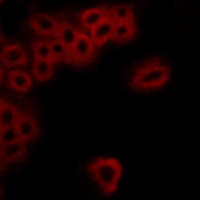

Immunofluorescent analysis of EP4 staining in MCF7 cells. Formalin-fixed cells were permeabilized with 0.1% Triton X-100 in TBS for 5-10 minutes and blocked with 3% BSA-PBS for 30 minutes at room temperature. Cells were probed with the primary antibody in 3% BSA-PBS and incubated overnight at 4 °C in a hidified chamber. Cells were washed with PBST and incubated with a AF594-conjugated secondary antibody (red) in PBS at room temperature in the dark.